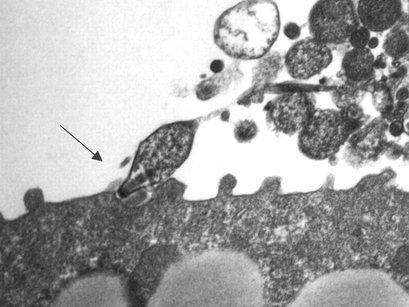

mycoplasma pneumoniae